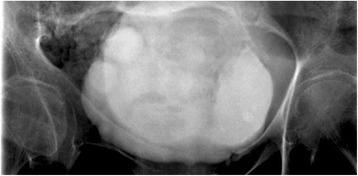

Emphysematous cystitis is a very rare complicated urinary tract infection characterized by air in the bladder wall.

We report two clinical cases of emphysematous cystitis of an 83-year-old Caucasian woman with diabetes mellitus and a 78-year-old Caucasian man with no past medical history. They presented with severe confusion and abdominal distension. Emphysematous cystitis was diagnosed in time with a thorough physical examination, urine analysis and computed tomography. The patients were successfully treated with antibiotic therapy and bladder drainage.